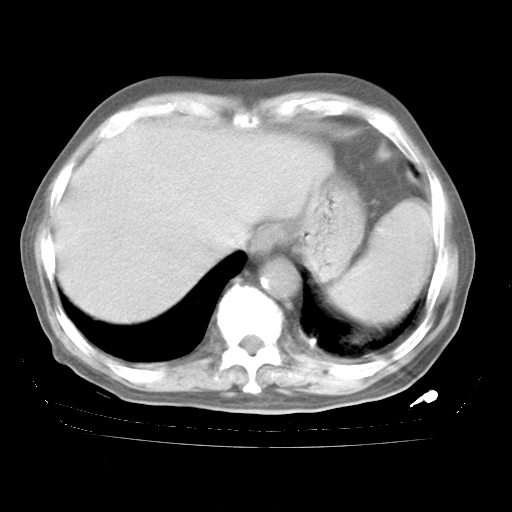

4月28日肺部CT——再次出现类似去年5月9日——透光度降低,“间质性”改变。

4月28日肺部CT——再次出现类似去年5月9日——磨玻璃样、间有“粟粒样”改变。

4月28日肺部CT

个人阅读4.14日肺部CT平扫:纵隔窗无异常,但肺窗示:双下肺内、后基底段有片絮状侵润影,部位以后基底段为著,以间质改变为主,呈急性肺泡炎征像,和首次住院影像学有相似之处。仅是个人读片,明日请相关专家再读片哈。其它建议同上。

1、108#的是4月14日的胸部CT(发此贴时还没看着28日的CT)。14日的胸部CT其实已经出现改变(如108#所述),个人认为28日的胸部CT除纵膈窗疑似有双侧胸膜增厚或少量胸积液(可行胸部B超明确)外,与4月14日对照病变有所加重;2、已经给予“异烟肼、利福平、乙胺丁醇”抗痨治疗?如果是,甲强龙80mg可缓慢减量;如果环磷酰胺已停用,暂不使用;3、中性粒细胞92%,明显升高,目前体温情况?注意合并细菌感染可能,使用左氧氟沙星情况下,是否联用B-内酰胺类抗菌药物?另外是查免疫全套非风湿全套。

今请临免主任会诊后认为:4月14日胸部CT已有双下肺间质性改变。患者病情复发多系激素减量过快不正规所致。目前甲强龙80mg/日,一周后酌情开始减量,不易过快。环磷酰胺若已停用,暂不使用。他同意目前抗菌药物使用,但应考虑是否加用B-内酰胺类抗菌药物(中性细胞明显增高);2、结核复发目前依据不足;3、若免疫全套各项指标正常,考虑多系特发性肺间质炎可能大。4、加强支持,并注意保护胃黏膜。

今上午去请教了临免、呼吸主任:1、介绍病史和阅读系列胸部CT一致认为:患者肺结核不考虑,仍为肺间质纤维化,目前处于急性肺泡炎阶段。2、若仍发热,可将甲强龙增至:80mg Bid静滴,同时鉴于中性增高,合并细菌感染可能,继续左氧氟沙星治疗,再联用B-内酰胺抗菌药物,如头孢哌酮--舒巴坦;3、停用抗痨药;4、目前甲强龙每日剂量160mg ,体温正常后再酌情减量;目前暂不用免疫抑制剂;4、不建议使用免疫增强剂等;5、加强支持治疗,鼓励患者进食;5、注意随访肝、肾功及血常规情况;6、因患者目前激素用量较大,加用胃黏膜保护剂,防止消化道出血可能。